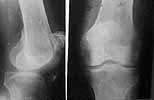

However there are some features: at the same side there is deficiency of the patellar tendon with the patella fixed to the femur, and active knee extension is absent.

2. Explore left knee/extensor mechanism. If adequate patellar tendon/ quad tendon integrity and at least 60 degrees arc of motion (including full extension), I would attempt extensor mechanism repair/reconstruction (the specifics would depend on the exact findings). If repair/reconstruction not feasible or ROM too limited I would proceed to knee arthrodesis, at which time 1-2 cm shortening of left side could be done.